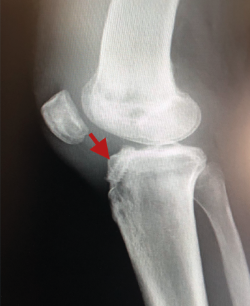

El tratamiento de un paciente que sufre una rotura aguda del LCA (Figura 2) sigue siendo motivo de discusión(9). Hay muchos condicionantes que influyen en el manejo terapéutico de estas lesiones (ya sea quirúrgico como no quirúrgico), como son la edad, la ocupación, la actividad deportiva, las lesiones asociadas, el grado de laxitud de la rodilla, las expectativas o las recidivas de la lesión, entre otras. El riesgo de artrosis tras la rotura aguda del LCA será mayor en ambos grupos con respecto a la población sana, sea cual sea el tratamiento(12). Los factores de riesgo más importantes para el desarrollo de artropatía son: lesión meniscal, meniscectomía e injerto hueso-tendón-hueso (HTH).

Figura 2. Rotura aguda del ligamento cruzado anterior.